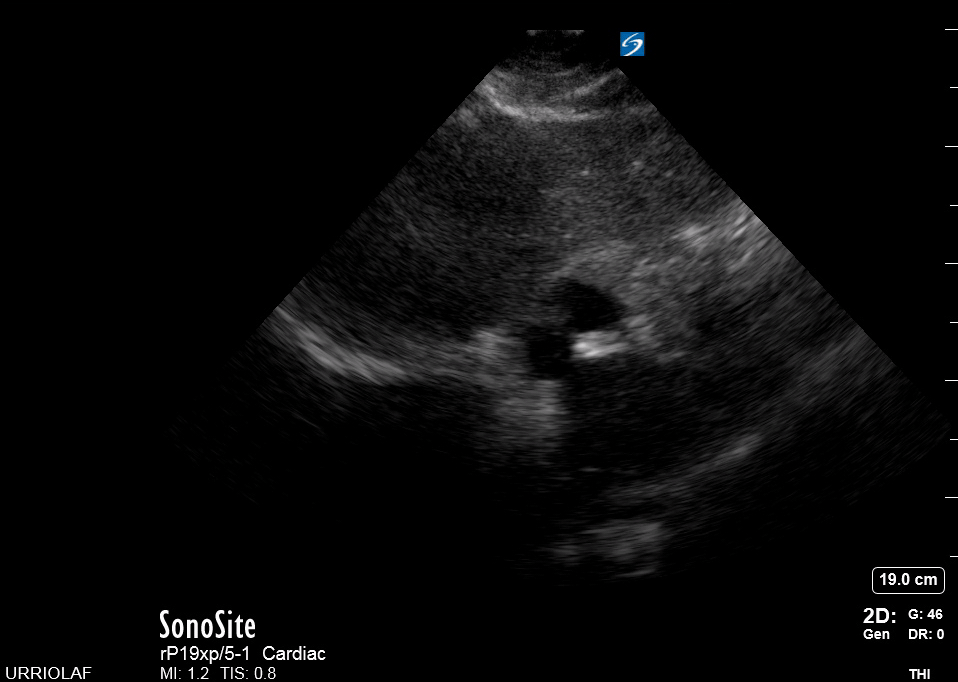

This view looks at the heart from the apex. When done properly, it achieves a horizontal cut of the heart that demonstrate all four chambers simultaneously. Consequently, its main utility is to assess the relationship between LV and RV. Beware, differentiating the chambers by ventricle size or thickness is not recommended, and it could lead to confusion in case of RV enlargement.

ORIENTATION & TECHNIQUE

Place the transducer at the apex beat and angle it towards the right scapula. The correct image results from sliding the probe until the interventricular septum is in the middle of the screen, vertically dividing both sides of the heart. If using a cardiac preset, the probe’s marker points towards the patient’s left arm. Simpler, in this view, the probe notch should meet the marking on the screen, which is fundamental to avoid confusion.